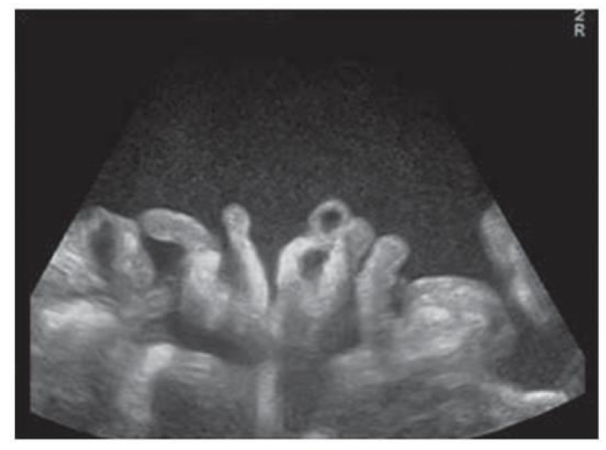

What kind of ascites is shown in this image?

Complex ascites

What type of ascites is shown in this image?

Exudative; fluid is speckled